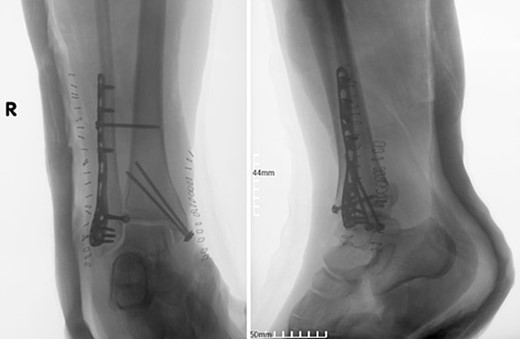

A surgical treatment was decided, consisting of ORIF of the fracture which was addressed within 48 hours of the admission to the hospital. Fracture reduction was achieved through a lateral and medial approach to the lateral and medial malleolar, respectively. A 3.5-mm neutralization plate with a lag screw was applied on the lateral malleolus combined with a 3.5-mm lag screw fixation of the medial malleolus and a 3.5-mm syndesmotic screw fixation (Fig. 2).

Postoperative anteroposterior and lateral X-ray of the ankle joint after ORIF of the fracture.